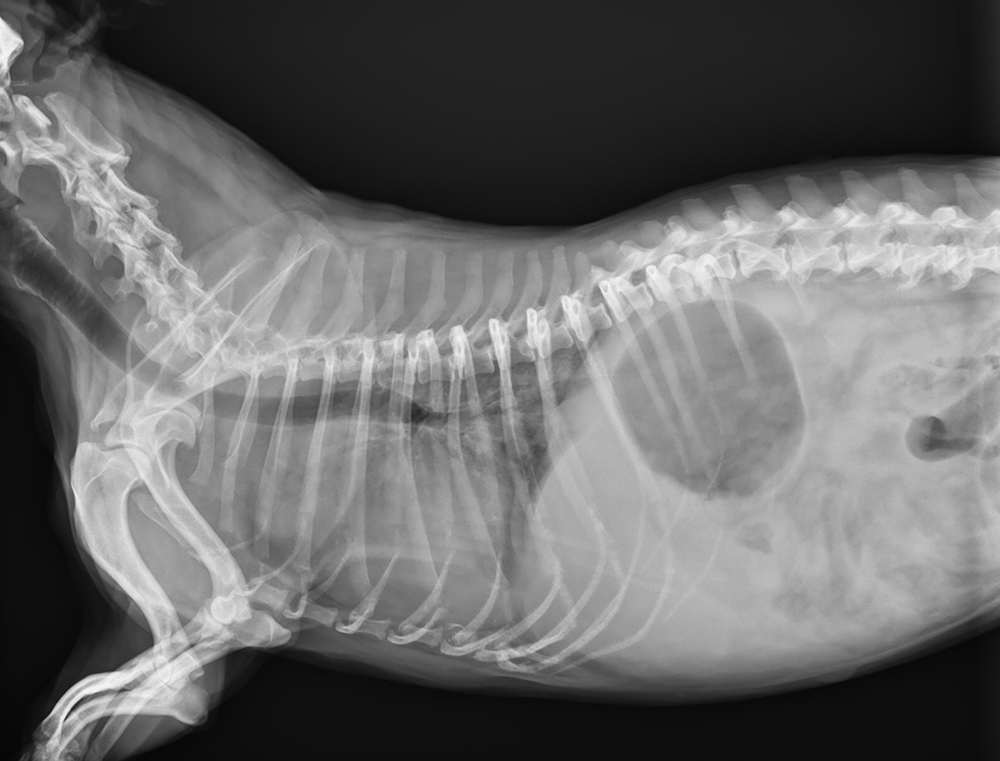

上海鵬峰寵物醫(yī)院